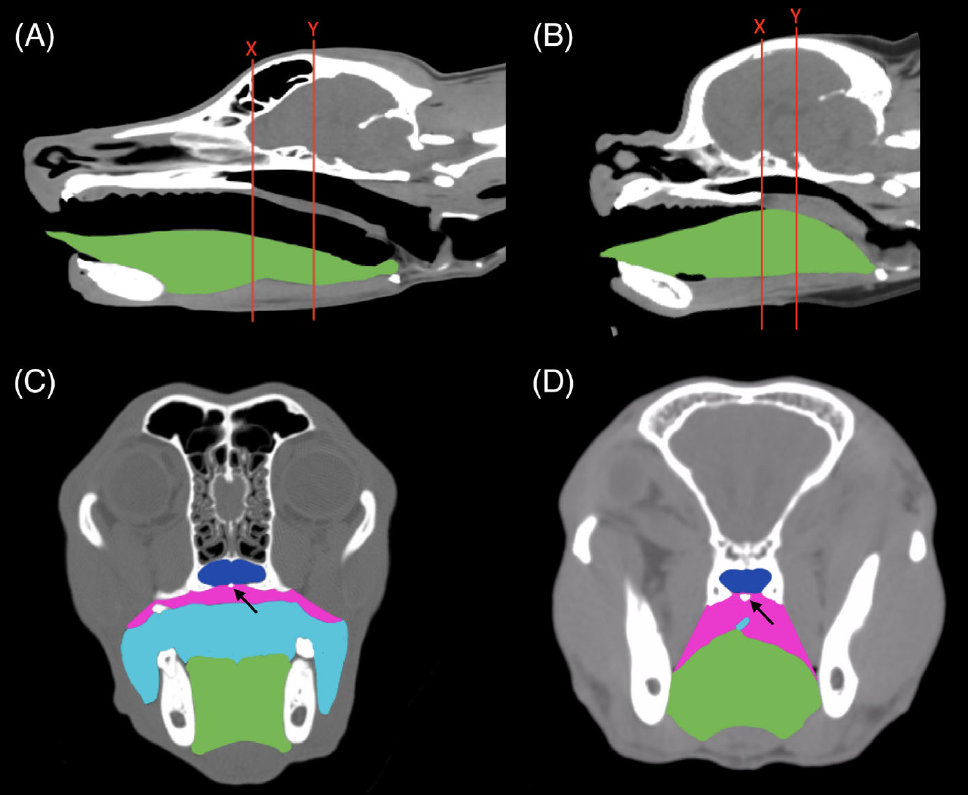

Durante la sedación de pacientes braquicefálicos es extremadamente importante realizar una vigilancia intensiva, una correcta monitorización y emplear dispositivos que mantengan la vía aérea despejada (Foto 1). La macroglosia de estos pacientes facilita la obstrucción de la vía aérea cuando el paciente está sedado (Foto 2).

Foto 2: Imagen de TC que compara un paciente mesocefálico (A y C) y uno braquicefálico (B y D), muestra la nasofaringe (azul oscuro), el grosor del tejido palatal (rosa), la orofaringe (azul claro) y la lengua (verde).